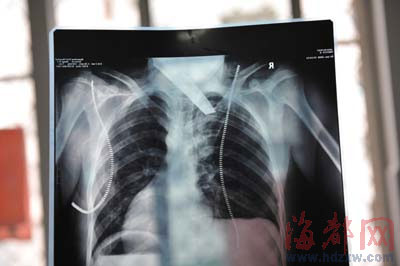

前晚,在第一醫(yī)院急救室,經(jīng)過4個多小時的搶救,醫(yī)生將匕首從小勇身上取出,發(fā)現(xiàn)這把匕首的刀尖扎斷了1厘米。由于小勇肺部被刺中,昨天上午,醫(yī)生再次進行了3個多小時的手術(shù),切除了受傷的部分肺,直到下午,小勇才挺過來!巴α艘灰梗F(xiàn)在總算醒了過來!睏钆恳灰箾]睡,守在手術(shù)室外7個多小時,生怕兒子再醒不過來。不過,由于傷勢嚴(yán)重,小勇目前戴著氧氣呼吸,仍未脫險。